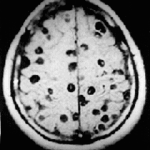

Labortests und bildgebende Untersuchungen spielen eine wichtige Rolle bei der Bestätigung der Diagnose und der Beurteilung des Schweregrads von durch Herpesviren verursachten Augenkrankheiten. Zu den relevanten Labortests gehören Viruskulturen, die Polymerase-Kettenreaktion (PCR) und Antigen-Nachweistests aus Augenabstrichen oder Kratzern zum Nachweis des Herpes-simplex-Virus (HSV) oder des Varizella-Zoster-Virus (VZV). Darüber hinaus können Serum-Antikörpertests durchgeführt werden, um IgM- und IgG-Antikörper gegen Herpesviren nachzuweisen, die wertvolle Informationen über frühere oder aktuelle Infektionen liefern. Bildgebende Verfahren wie die optische Kohärenztomographie (OCT) und die Ultraschall-Biomikroskopie (UBM) können zur Beurteilung der Hornhautdicke, der Vorderkammertiefe und der intraokularen Strukturen bei schweren Entzündungen oder vermuteten Komplikationen wie Hornhautödem, Uveitis oder Retinitis eingesetzt werden. Fluoreszeinangiographie und Fundusfotografie können angezeigt sein, um die Gefäße der Netzhaut zu beurteilen und Anzeichen einer Beteiligung des hinteren Segments zu erkennen.